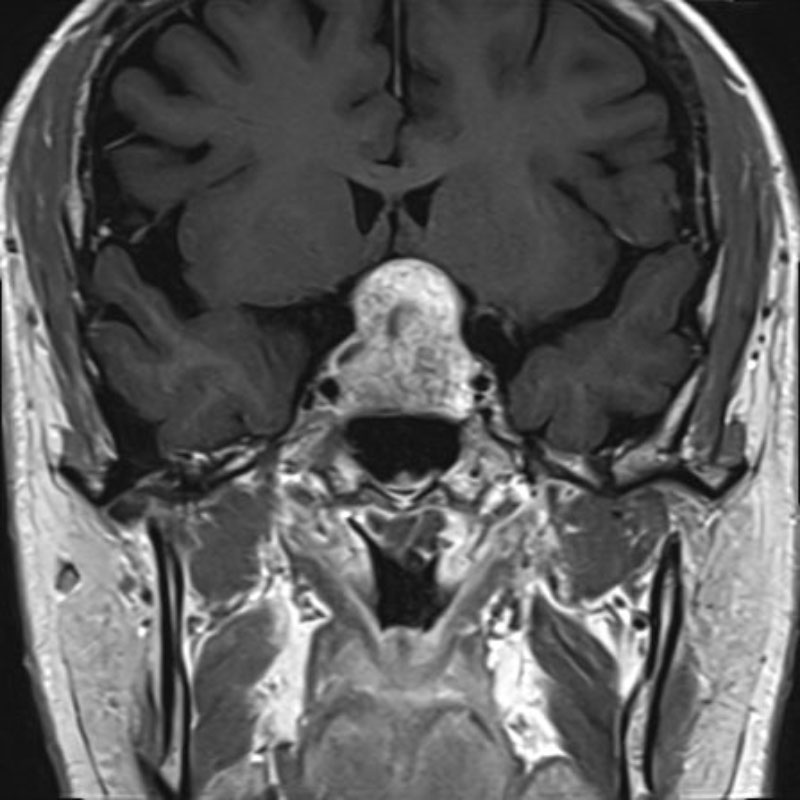

断層撮影

手術前1

手術前2